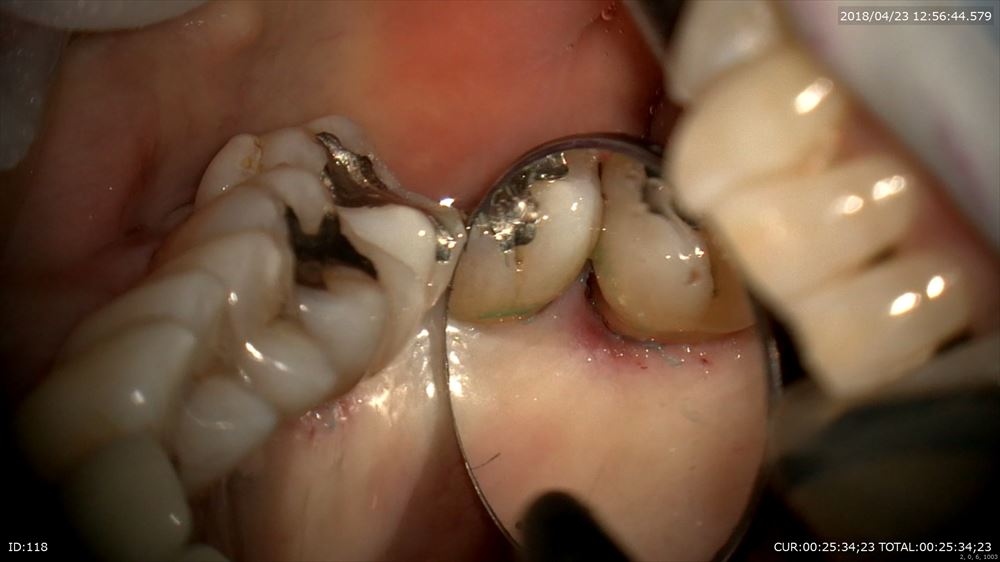

この様に歯茎を切らずに歯肉溝からのアプローチ。この器具ミラーの役割もします。

歯根形態がこのように見えるからデブライドメントも、「なんとなく」ではなく歯根にきちっと合わせて行えます。

こんなにデブライドメントしてもこの様に乳頭も傷をつけず

切り傷などありません。裸眼やルーペとは丁寧さの次元が違います。だから痛くない!!!